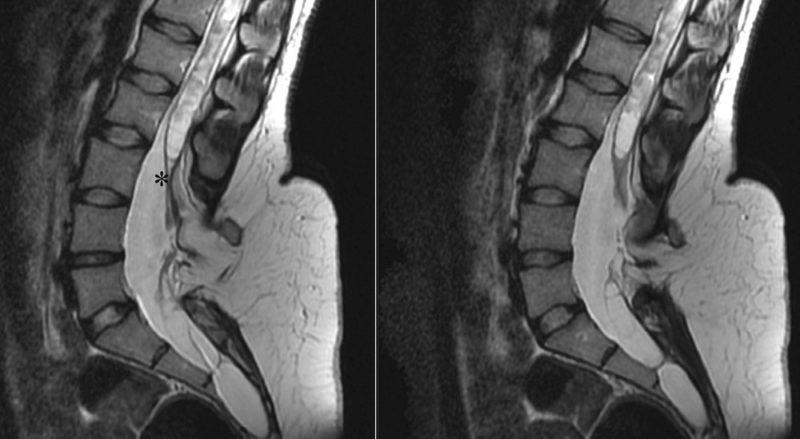

| Грыжа межпозвонкового диска | Сдавление спинного мозга или нервных корешков, изменение формы межпозвонкового диска, возможно наличие фрагмента диска в спинномозговом канале | Отек окружающих тканей, изменение интенсивности сигнала в поврежденном диске |

| Стеноз спинномозгового канала | Сужение спинномозгового канала, сдавление спинного мозга | Атрофия спинного мозга, изменение интенсивности сигнала в спинном мозге |